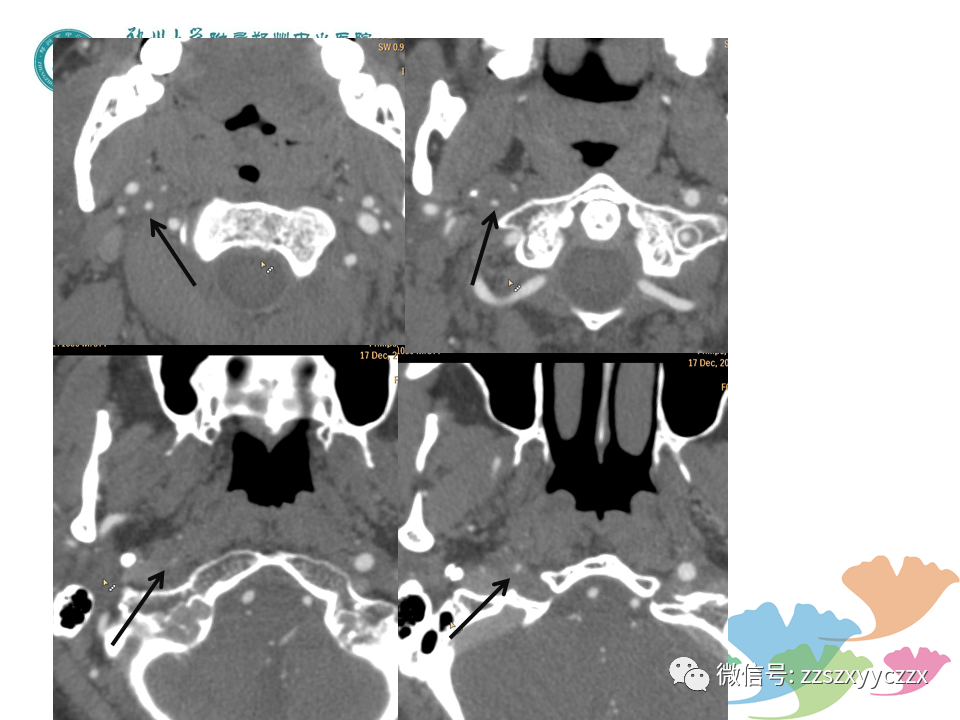

按摩、外伤及不良姿势等是CAD常见原因;本文通过3个病例阐述了颈动脉夹层的超声诊断,也对1例主动脉缩窄的超声学、CTA进行了描述,和大家分享。